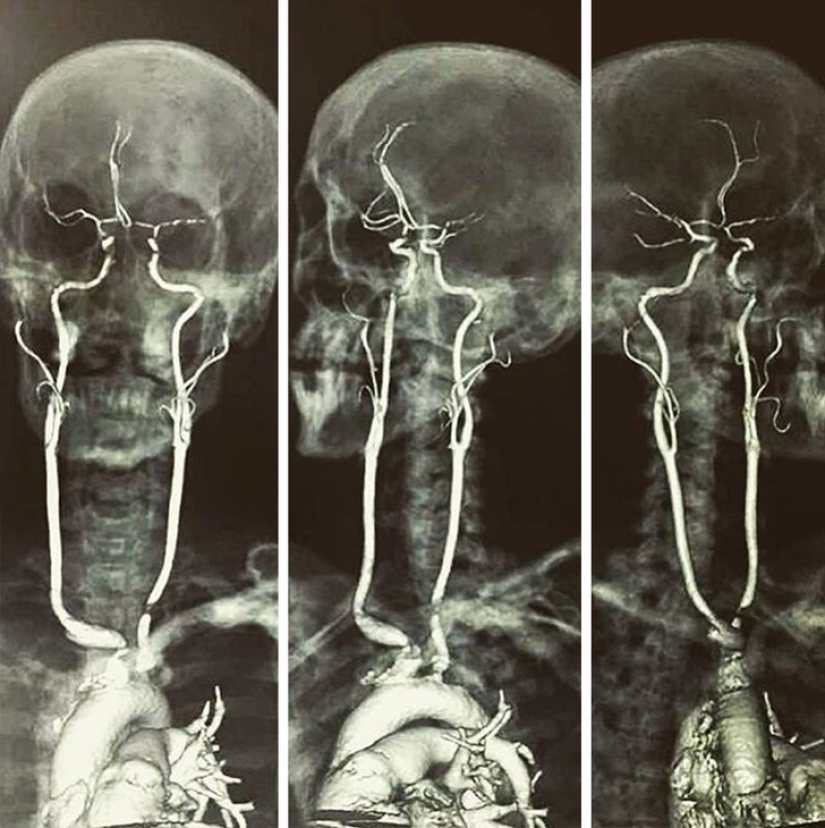

Así es como se ven las arterias carótidas.